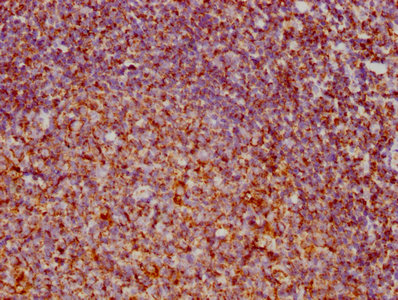

Immunohistochemistry of paraffin-embedded human liver cancer using CSB-PA873646DSR1HU at dilution of 1:100

Immunohistochemistry of paraffin-embedded human pancreatic cancer using CSB-PA873646DSR1HU at dilution of 1:100